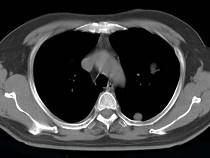

女性患者,42岁,1年前行肝癌手术,胸部CT扫描如图,应诊断为()A.肝癌肺转移B.肺结核球C.球形肺炎D.肺多发囊肿E.肺脓肿

问题 女性患者,42岁,1年前行肝癌手术,胸部CT扫描如图,应诊断为()

选项 A.肝癌肺转移 B.肺结核球 C.球形肺炎 D.肺多发囊肿 E.肺脓肿

答案 A